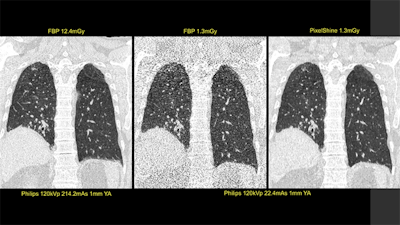

At its booth, Fujifilm Medical Systems Europe is highlighting the REiLI medical imaging and informatics AI initiative. The company is currently developing a number of AI technologies, such as Region Recognition for recognizing and extracting organ regions. Other works-in-progress REiLI applications include computer-aided detection for reducing image interpretation time and supporting radiologists' clinical decision-making, plus Workflow Support for optimal study prioritization, alerts for AI findings, and automated report population. Fuji is also offering live demonstrations of AI-enhanced radiology workflows in its booth. Another new Fuji AI application, FCT Pixel Shine, provides image processing of low-dose CT images.